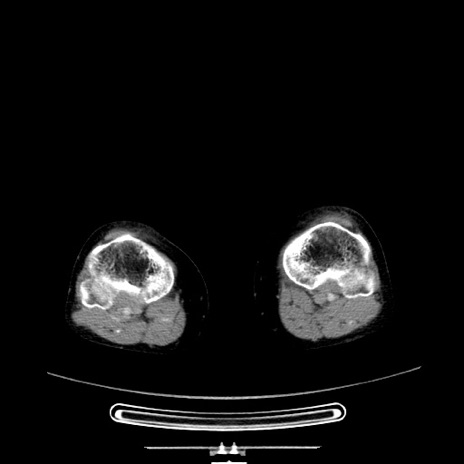

冠状断像